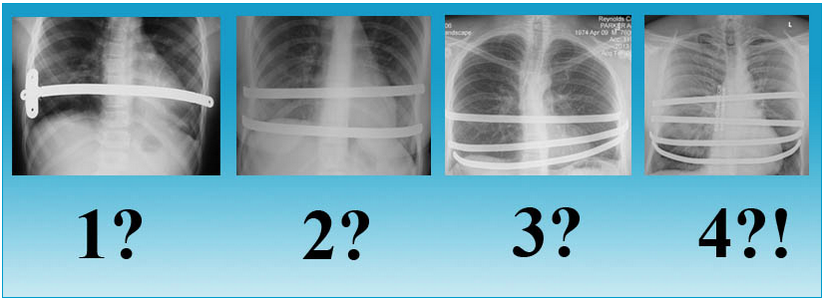

Отзывы пациенток, у которых была проведена коррекция деформации грудной клетки в клинике «Breast-Health» с помощью операции Насса, исключительно положительные. В ходе хирургического вмешательства исправляются дефекты второй степени, деформации соскового комплекса, серьезные ассиметричные изменения с дефицитом тканей. Используются корректирующие пластины длиной от 18 до 24 см.

Сколько пластин вы устанавливали большинству своих пациентов?

Изначально метод Насса был разработан для одной пластины. Но все чаще мне приходится использовать 2 и иногда даже 3 пластины. Причина в следующем: у пациентов с вогнутой грудиной создает давление, направленное вниз. Чем глубже вмятина или старше пациент, тем больше она вдавливается внутрь. При использовании единственной пластины для коррекции создается очень сконцентрированное локализованное давление в одном месте, а также есть тенденция к перевороту пластины из-за того, что она находится под сильным натяжением. Поэтому при использовании нескольких пластин ощущения пациента менее болезненны и меньше шансов переворота пластины. Также есть свидетельства, что установка нескольких пластин дает более удачный косметический эффект. Хотя для молодых пациентов с небольшими деформациями одной пластины может быть вполне достаточно.